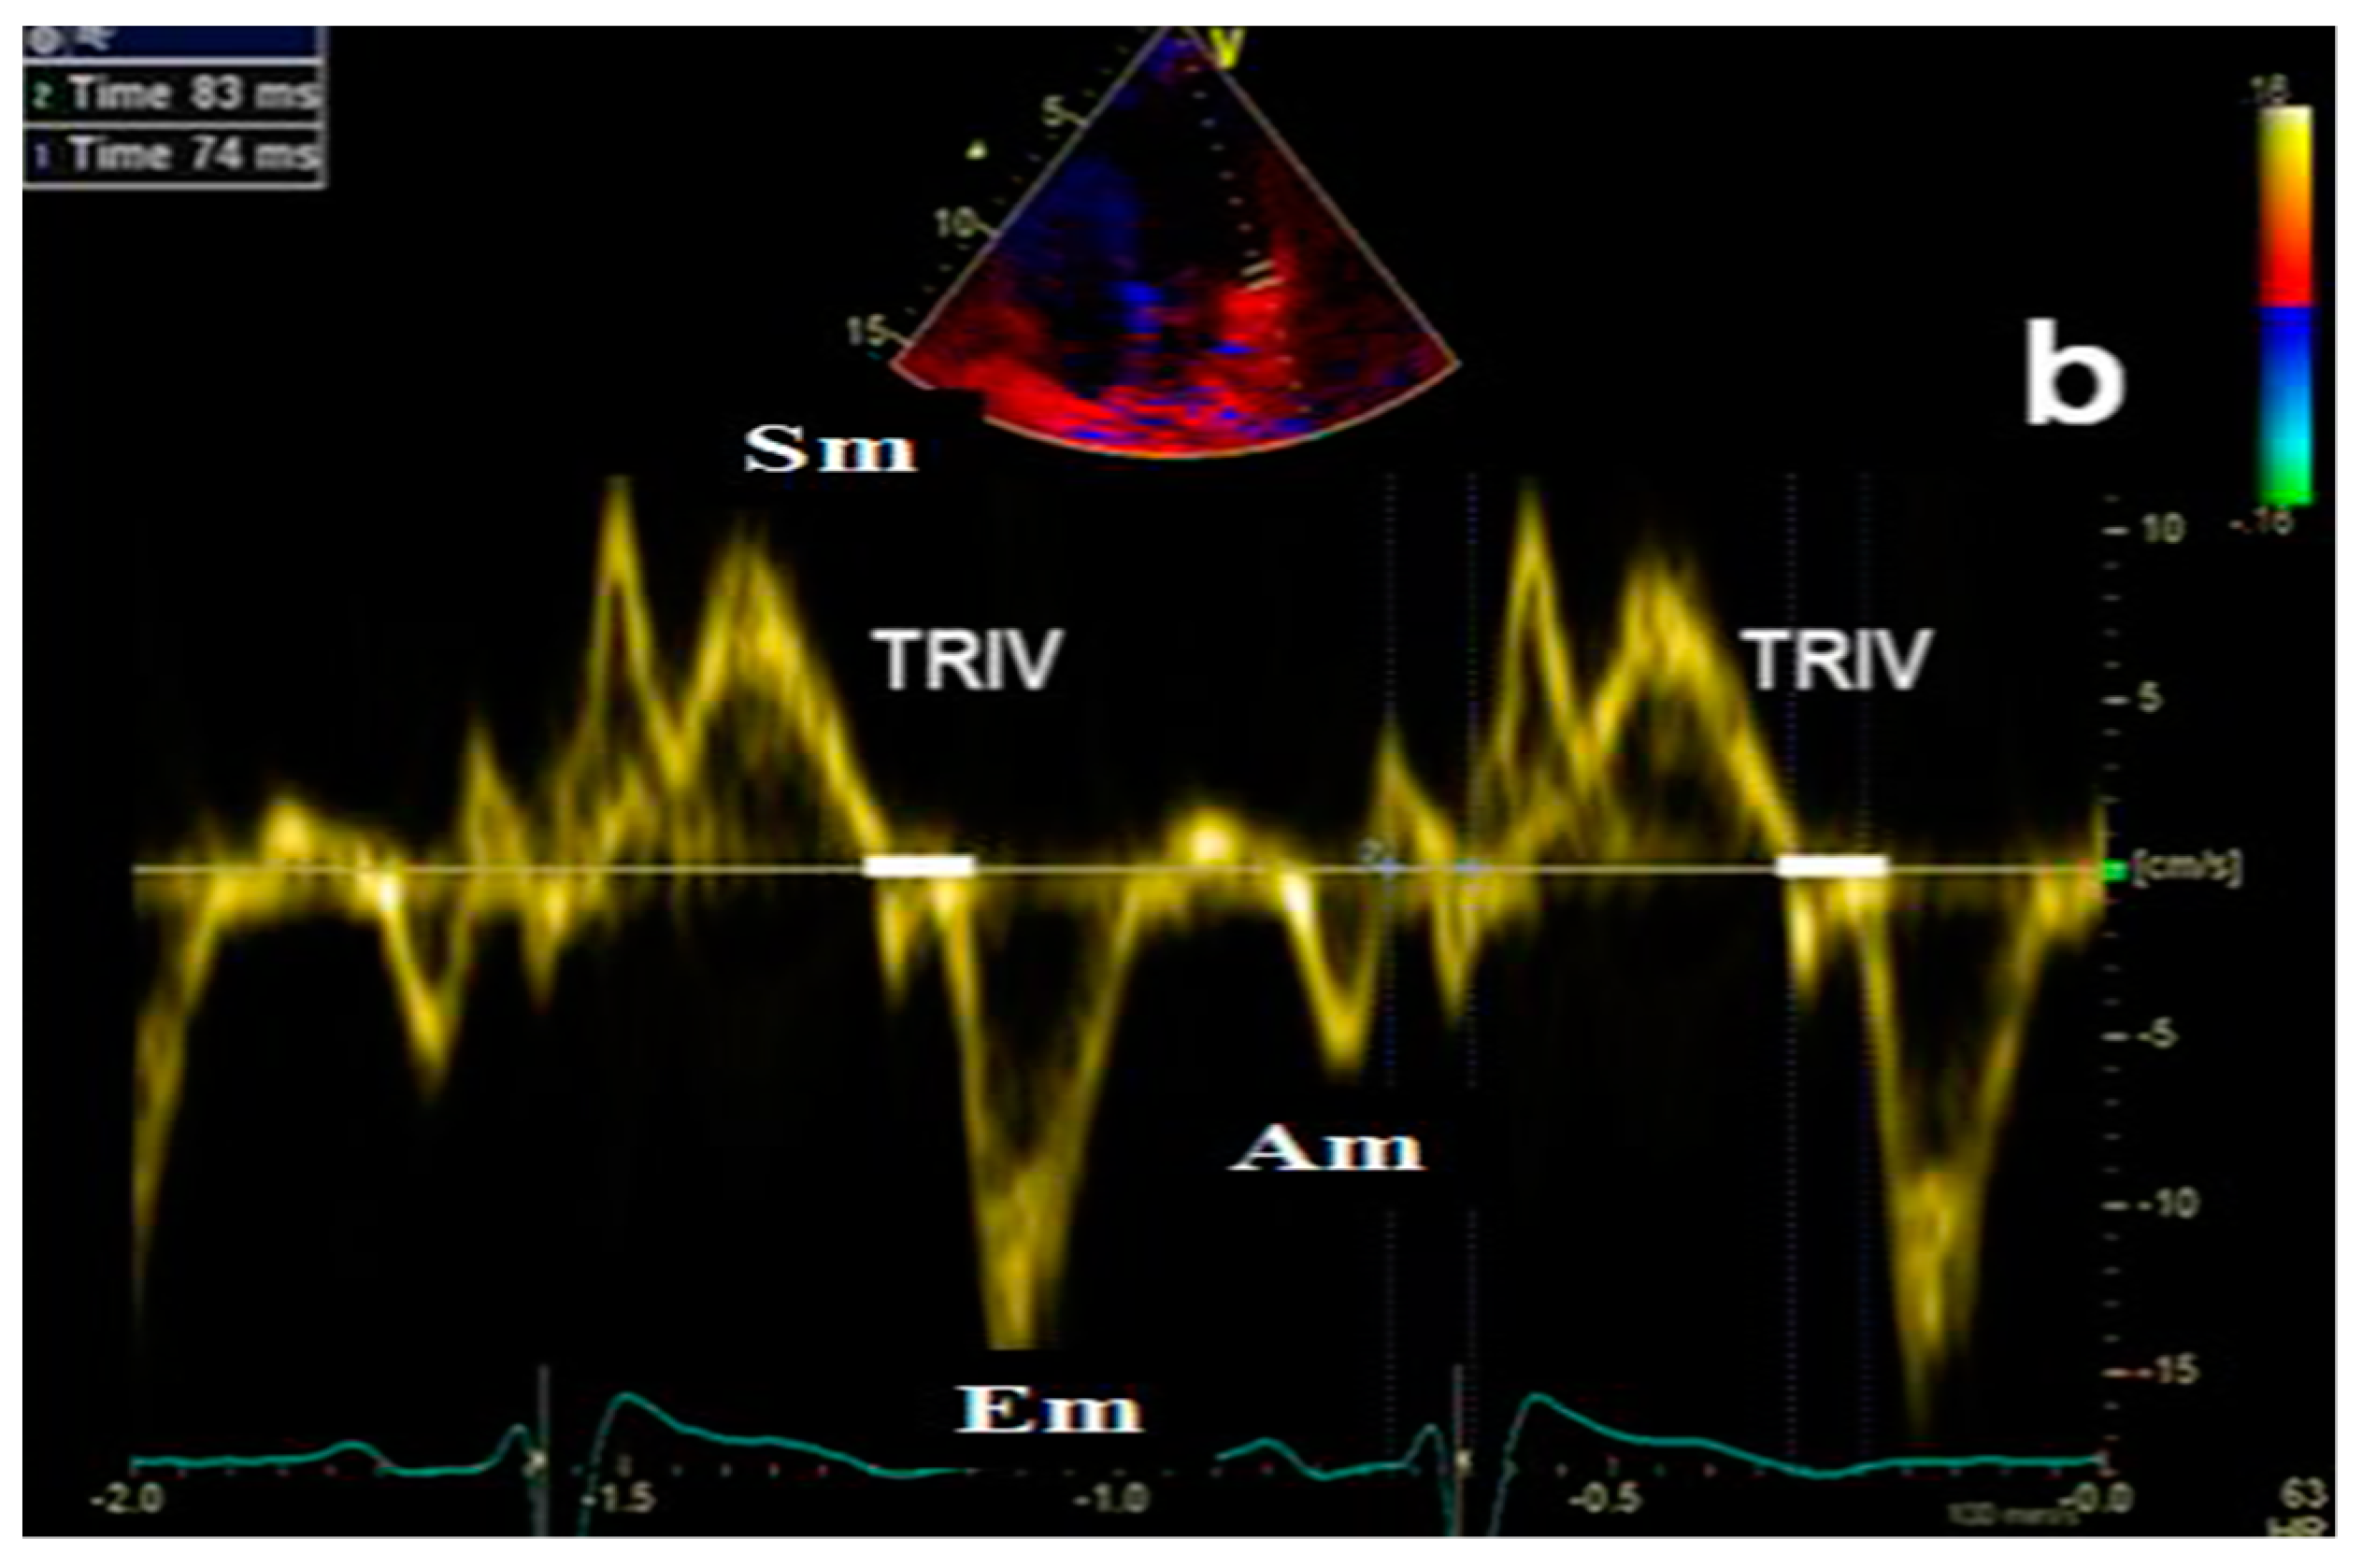

- Isovolumetric relaxation time (IVRT) (Figure 4), early diastolic annular velocity E’ (septal, lateral, and average), late diastolic annular velocity A’ (septal, lateral, and average) via tissue Doppler imaging (TDI) (which measures myocardial tissue velocities during the cardiac cycle);